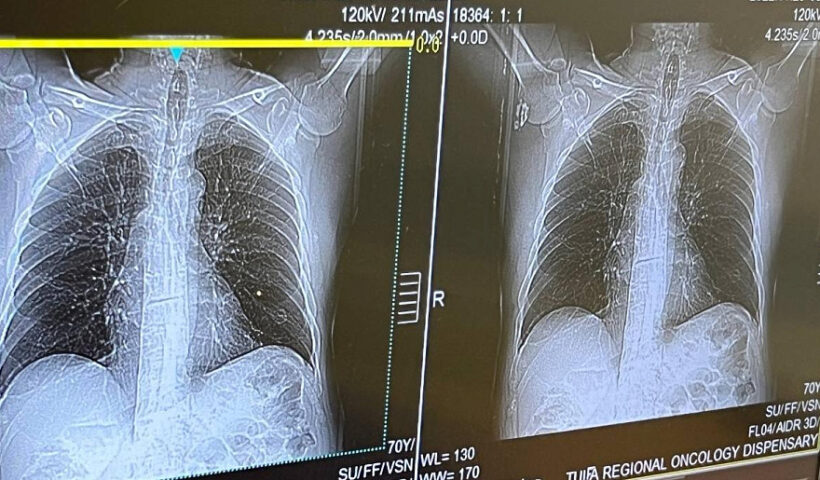

«Самыми частыми среди таких заболеваний являются пневмония, хроническая обструктивная болезнь легких и бронхиальная астма. Для большинства заболеваний легких характерна сезонность. И сейчас наступило время, когда происходит рост заболеваемости пневмонией — по сравнению с летним периодом примерно в три раза», — сказал заведующий пульмонологическим отделением областной больницы Арсен Басилая.

В этом году в Тульской области диагноз «пневмония» подтвержден почти у 3 тысяч человек. Это серьезное и опасное заболевание. Его вызывают различные микроорганизмы — бактерии, вирусы и микроскопические грибы.